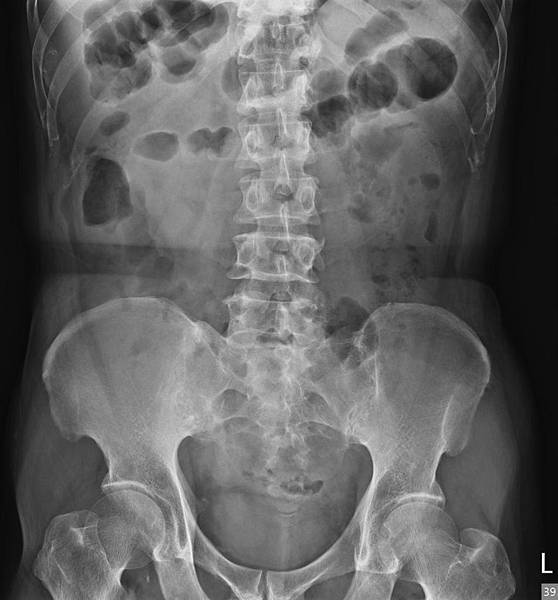

KUB看不出她的病有多嚴重:

看到這些抽血數值,大家都會猜急性闌尾炎。

如果KUB顯示大腸糞便不多,這種胃酸逆流怎麼治療?

這種胃酸逆流的原因可能是大腸細菌引起慢性發炎,Cytokine刺激胃酸異常分泌,治療的方式: